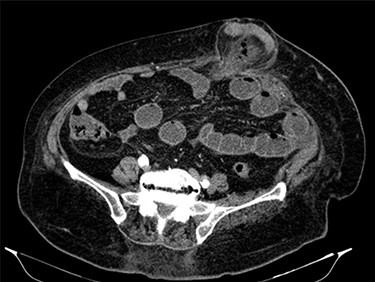

Fluid resuscitation measures, monitoring of urine output and pain control were initiated. Analytically, she had leukocytosis of 227 000/μl with neutrophilia 89%, elevated C-reactive protein 27.1 mg/dl and acute kidney injury with creatinine 1.8 mg/dl and urea 96 mg/dl. Arterial blood gas analysis showed no acidosis, respiratory failure or hyperlactatemia. The computed tomography (CT) scan identified an umbilical hernia containing a small bowel loop, evidenced densification of the hernia fat and some bubbles of extraluminal gas were also present (Fig. 2). An image of high-density and filiform morphology compatible with an FB (Fig. 3) was also identified. Images were consistent with dilation of the proximal intestinal loops, which suggested bowel occlusion.

Abdominal CT: image of high-density and filiform morphology compatible with FB.